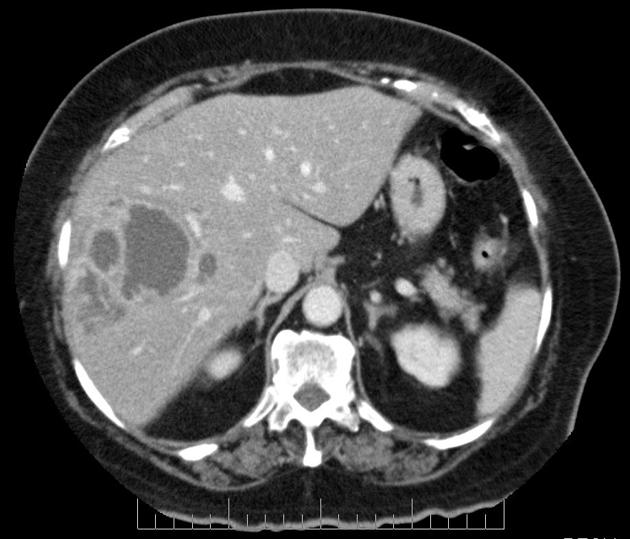

Hepatic abscesses, like abscesses elsewhere, are localised collections of necrotic inflammatory tissue caused by bacterial, parasitic or fungal agents. Introducción: el absceso hepático amebiano es la manifestación . El diagnóstico diferencial se relaciona con absceso piógeno, subfrénico, piocolecisto. Absceso Hepático Amibiano Ha disminuído la frecuencia 25% tienen antecedente de diarrea Más frecuente en hombres Más frecuente en LHD Absceso único.

An Med Interna Madrid ; 5: Si continua navegando, consideramos que acepta su uso. Amoebic abscesses are more common in a sub-diaphragmatic location and are more likely to spread through the diaphragm and into the chest. Rev Esp Enferm Dig ; During the two decades studied, 45 patients were diagnosed with PLA caused by bacteria, and there were 13 cases of ALA.

For patients with intermediate-stage B disease who have multinodular tumors without symptoms, no portal invasion, extrahepatic spread, or lymph node involvement, the recommended treatment is transarterial chemoembolization. In addition, predisposing diseases and the origin of abscesses for pyogenic abscesses 45 casesand associated diseases, epidemiological history of travelling to areas with a high prevalence of amoebiasis, the origin of patients, and the time between having been to endemic areas and the occurrence of symptoms in amoebic cases 13 cases were analysed.

Eur J Gastroenterol Hepatol, 10pp. It is an aggregation of multiple low attenuation liver lesions in a localised area to form a solitary larger abscess cavity. When the infection spreads to the liver through the portal veins it arises more commonly in the right lobe, probably due to an unequal distribution of superior and inferior mesenteric vein contents within the portal venous distribution.